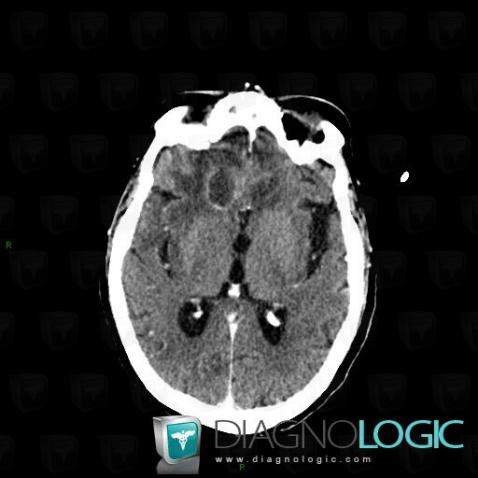

Encephalitis, Cerebral hemispheres, CT

Here is the specific information in the key image above:

- Diagnosis Encephalitis, Location(s) Cerebral hemispheres, with gamuts Hypodense intracerebral lesion on noncontrast CT